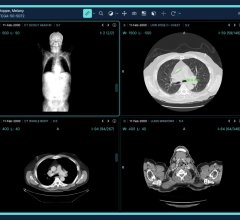

Even before the pandemic began to spread, the idea of offering radiologists the flexibility to work from home was trending. When COVID-19 enforced social distancing and new work behavior, it kicked this trend into high gear. Working from home helps limit exposure to the virus while still allowing radiologists to read as if they were on-site. The first challenge is creating home reading solutions that are the same level of quality, security and performance radiologists get from a medical workstation in the hospital reading room. The second challenge is getting them set up in a timely manner.

Barco and VisionTek partnered to develop a solution specifically designed for remote radiology reading that tackles both challenges. Together, they are undertaking the issues of technology compatibility and performance, security and patient privacy, as well as quality and compliance. Their home read solution has attracted immediate attention and early adoption in the hospital community.

The VisionTek Thunderbolt 3 Mini eGFX Enclosure comes in a sleek and portable design that discretely sits on a desk, or hidden away, to handle graphic intensive medical scan applications. Combined with a pre-installed Barco MXRT-display controller, VisionTek’s Thunderbolt 3 Mini eGFX Enclosure can accelerate the most demanding medical scan software programs.

“This configuration is seamlessly deployable and mirrors the hospital reading environment providing the same diagnostic confidence and medical compliance maintained within hospital walls,” reported Mike Sklar, VP Healthcare Sales for the Americas at Barco. “It’s paired with Barco’s QAWeb Calibration and Monitoring Software, which is the industry's first and only web-based service for high-grade Quality Assurance.”

"VisionTek’s Mini eGFX enclosure powered by Barco MXRT series graphics boards and diagnostic displays allow Radiologists to remotely read scans in the safety of their home office." stated Michael Innes, President, VisionTek Products, LLC. “VisionTek is very proud to play a small part in technology innovation that impacts some of the most critical healthcare applications within the radiology community.”